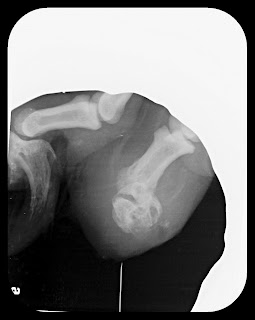

This protocol was followed, but later the debris came back. A thorough ear flush was performed under anesthesia and pictures were taken while the ears were being cleaned. Note below a picture of one of the ears prior to cleaning. Following the deep ear flush, Abby was put back on the duck food as well as routine cleaning s followed by medications.